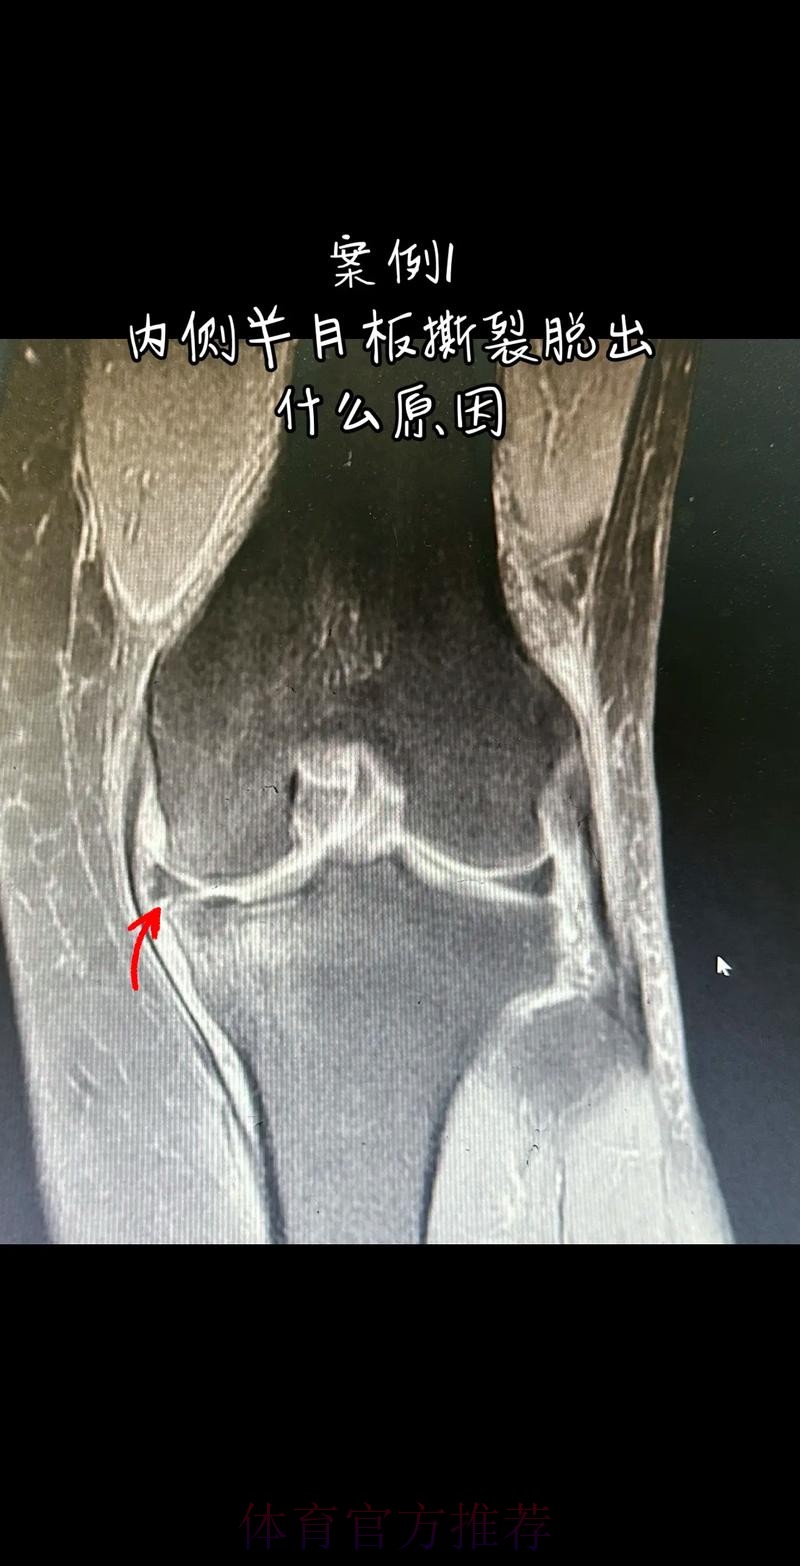

从医学角度看 半月板是膝关节内一块呈“C”形的软骨结构 其作用是缓冲冲击 稳定膝关节 并帮助分散压力 “左膝内侧半月板撕裂”通常说明在一次急停 旋转 或对抗中 半月板受到了超过其承受极限的力导致结构损伤 这类伤病常见于足球 篮球等需要频繁变向和对抗的项目 对于职业球员而言 半月板损伤严重程度不一 但共同点是都会影响支撑发力 跳跃以及变向时的稳定性 而官方给出的“预计伤缺6-8周”这个时间区间 往往对应的是中度损伤或通过微创手术加积极康复能够较快回归的情况 也意味着暂时没有出现必须长时间休战的最坏结果

表面上看 6-8周只是一个时间区间 但对顶级球队的赛程来说 这段时间可能包含多场联赛 甚至关键杯赛淘汰轮 相当于缺席一个赛季中最密集的一段周期 需要强调的是 这个“预计”并不是绝对数字 它取决于撕裂的位置 大小 修复方式 以及球员个体的恢复能力 有时若采取保守治疗 球员在6周时即可参与部分训练 但要达到比赛要求则可能接近8周甚至稍长 此外 精英运动员的康复不仅仅是伤口愈合 还包括力量恢复 协调重建 和心理自信的回归 阿拉巴要在有限时间内完成从“伤病患者”到“可靠首发”的角色转换 这一过程复杂程度远远超出一纸通告所能呈现

在“官方 预计伤缺6-8周”这段时间里 阿拉巴需要完成的康复目标可以概括为三个层面 首先是生理层面 半月板区域的疼痛与炎症控制 关节活动度的恢复 以及周围肌群力量的增强 其中股四头肌 腘绳肌与臀部肌群的力量对膝关节稳定至关重要 其次是功能层面 需要通过特定训练重新建立变向 跳跃 对抗中的信心 包括在接近比赛速度下的模拟对抗训练 最后是心理层面 对于一名习惯于每三天一战的球员 突然被迫远离比赛容易产生焦虑和不安 这时教练团队 家人和队友的支持就显得尤为重要 若这三个层面协调推进 他在伤缺期结束后能更自然地融入比赛节奏